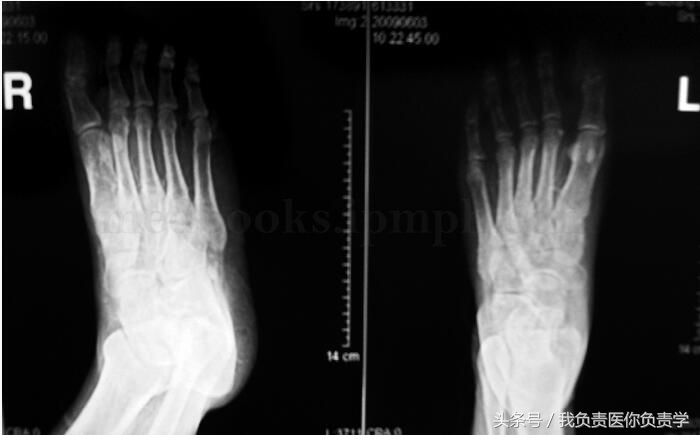

其他检查:左右足正斜位片:检查所见构成双足各骨骨质疏松,未见明确骨质增生及破坏,未见骨折,双足各关节未见异常。印象诊断双足骨质疏松。胸片(图35‐5):心、肺、膈未见异常。胸部CT:检查所见两肺透亮度减低,呈毛玻璃样改变,以双上肺明显,右下肺后基底段可见钙化点,余两肺未见结节及片状病灶,气管及叶、段支气管无狭窄,肺门、纵隔未见明确肿大淋巴结。心脏无扩大,胸膜无结节,胸腔无积液,胸壁未见确切异常。印象诊断:双肺呈毛玻璃样改变,考虑慢性肾衰竭引起心肺改变。泌尿系彩超:左肾区不纯液性包块;右下腹移植肾血流显示较稀少。下腹部CT:检查所见左侧髂窝可见移植肾,其形态、大小未见异常改变,移植肾内侧可见扩张的输尿管,前列腺形态、大小正常,内见散在钙化斑,膀胱充盈不佳,膀胱精囊角存在,直肠结构未见异常,盆壁未见肿大淋巴结,盆腔、双侧腹股沟区、双侧臀部血管广泛钙化。印象诊断:左侧髂窝移植肾形态、大小未见异常改变,左侧输尿管扩张积水;盆腔、双侧腹股沟区、双侧臀部血管广泛钙化。腹部CT(图35‐6):双肾皮质变薄,并见大量蛋壳样钙化,双肾盂、肾盏及左侧输尿管上段扩张积水;移植肾大小、位置、形态未见明显异常;腹部血管广泛钙化;胆囊结石。心电图(图35‐7):窦性心律,大致正常心电图。

图35‐5 X 线检查提示:双足骨质疏松